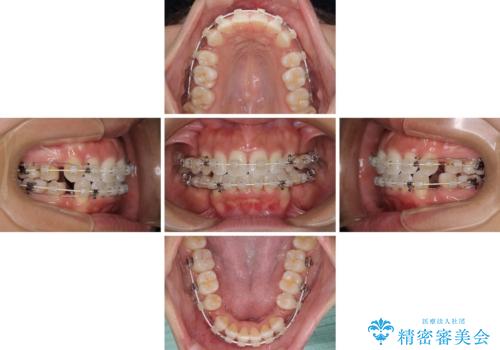

抜歯矯正で唇を閉じやすく 目立たないワイヤー装置

- 審美装置

- 2年3ヶ月

上下顎ともに前突した歯列であったので、上下ともに左右の第1小臼歯4本を抜歯し、ワイヤー装置にて矯正治療を行うこととしました。